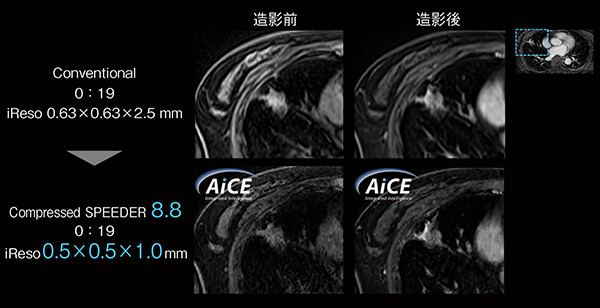

Compressed SPEEDERは、高速撮像技術であるparallel imaging(PI)と圧縮センシング(CS)を組み合わせて画質の劣化を防ぎ、高速撮像を実現する。AiCEとの併用によって画質を担保しながらさらなる撮像時間の短縮も期待できる。大野臨床教授は、「図2は、図1と同結節の造影前後のspoiled fast 3D T1-weighted imagingである“Quick 3D imaging(Quick 3D)”ですが、Compressed SPEEDERを使用することでTSCTやUTE-MRIと同等の分解能を有する画像を取得するとともに、AiCEを使用して良好な画質を担保することができます。Compressed SPEEDERは、PIとCSを融合させた高速撮像技術で、wavelet変換における閾値の低減を行うことで画質劣化を抑えた高速撮像が可能であり、時間分解能の向上にも有用です。本症例では、空間分解能を増加させているためSNRが低下する傾向にありましたが、AiCEを使用することで、空間分解能を向上した場合の画質劣化を改善できています。Compressed SPEEDERとAiCEの併用によって、時間分解能と空間分解能の向上を同時に行うことが期待できます」と評価する。さらに、Compressed SPEEDERとAiCE の組み合わせについては、「当院の研究でもAiCE はPIよりもCompressed SPEEDERとの相性が良いという結果が報告されており3)、併用することでさらに画質の改善と検査効率の向上が可能です」(大野臨床教授)と期待する。

図2 Compressed SPEEDER+AiCE